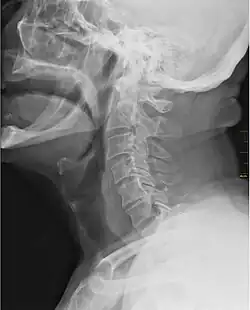

![]() Imagine cu raze X reprezentând gâtlejul (partea închisă la culoare din fața spinării) | |

În anatomia vertebratelor, gâtlejul este partea interioară a gâtului, situat în fața vertebrei. Acesta conține faringele și laringe. O secțiune importantă este epiglota, care este o clapă ce separă esofagul de trahee în scopul prevenirii inhalării băuturii și a mâncării în plămâni.[1] Gâtlejul conține diverse vase sangvine, mușchi faringieni, amigdaliene nazo-faringiene, amigdale, palatine uvulare, partea superioară a traheei și a esofagului și corzile vocale.[2] Gâtul mamiferelor este format din două oase, osul hioid și clavicula. „Gâtlejul” este uneori considerat a fi sinonim pentru istmul fauces.[3]